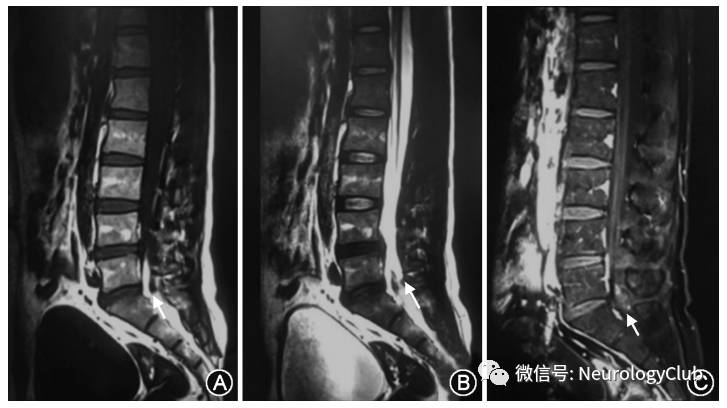

患者男性,28岁,农民,有羊接触史,因“双下肢无力14个月,加重4个月”于2017年1月10日收入我科。患者于2015年11月无明显诱因急性起病,表现为双下肢无力,不能行走,言语模糊,有一过性幻觉,反应慢。随后患者在当地医院查出布鲁杆菌阳性,并给予抗菌治疗、多西环素100mg静脉注射2次/d。治疗半个月后,患者双下肢无力现象得到缓解,可以下床拄拐走路,但有小便费劲,遂出院。患者于2016年9月病情加重,再次出现双下肢无力、发沉,无法自行走路,为求进一步诊治入我院。患者自患病以来无发热,无头痛头迷,无意识障碍,无恶心呕吐,无视物不清,无视物成双,无耳鸣,无饮水呛咳及吞咽困难。精神状态可,饮食睡眠可,大便无知觉,小便尚可,近期体重无明显减轻。入院体检:意识清楚,语言流利,双侧瞳孔等大同圆,对光反射灵敏,颈强阴性。双上肢肌力、肌张力正常,双下肢肌力均为IV级,肌张力正常。双侧肱二头肌反射亢进,肱三头肌、膝腱、跟腱反射正常。双侧巴宾斯基征阳性。深浅感觉未见确切异常。辅助检查:颈椎MRI平扫+增强示颈胸髓段蛛网膜下腔内见不规则结节状略短T2信号结节(图1A、B),增强后可见环状,结节状明显强化,肉芽肿形成可能大(图1C);脊膜增厚,蛛网膜局限黏连扩张,颈髓及T1-4水平胸髓内水肿,炎性改变(图1D、E),增强后未见明显强化影(图1F)。腰椎MRI平扫+增强示:L5-S1水平椎管内可见多发结节状长T1、短T2信号结节影(图2A、B),增强扫描后可见较明显强化(图2C);马尾神经增粗强化。颅脑MRI平扫+增强无异常,肺CT平扫见右肺及胸膜陈旧性病变。床旁心电图示:窦性心律,I度房室传导阻滞,中度右偏电轴。检验结果示:血尿常规及肝肾功能未见异常,肿瘤标志物未见异常,虎红平板凝集试验显示血清布鲁杆菌病抗体阳性,滴度1∶200(+)。

图1:患者颈椎MRI平扫 +增强(矢状位),C2处蛛网膜下腔可见不规则结节,T1略低信号,T2低信号,脊髓空洞形成(箭头,A、B) ;增强后可见不规则结节环状结节状明显强化,脊膜可见强化(箭头,C) ; 颈髓及T1-4胸髓弥漫增粗,蛛网膜下腔宽窄不等,信号欠均匀,T1略低信号,T2高信号(箭头,D、E);增强后无强化,考虑蛛网膜下腔粘连水肿导致的炎性改变(箭头,F)